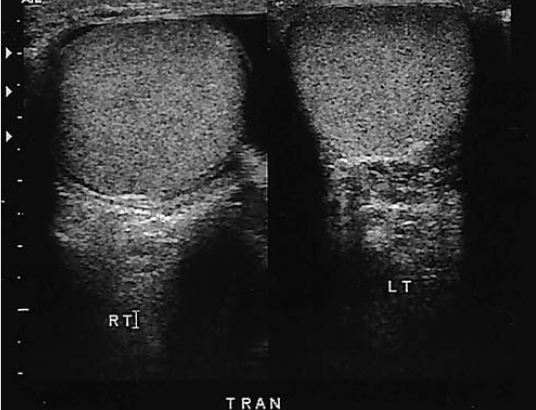

a 70-year old man presents with history of scrotal enlargement. He denies trauma to the scrotum or groin areas. On the basis of this clinical history, the sonographic findings are most sus for

hydrocele